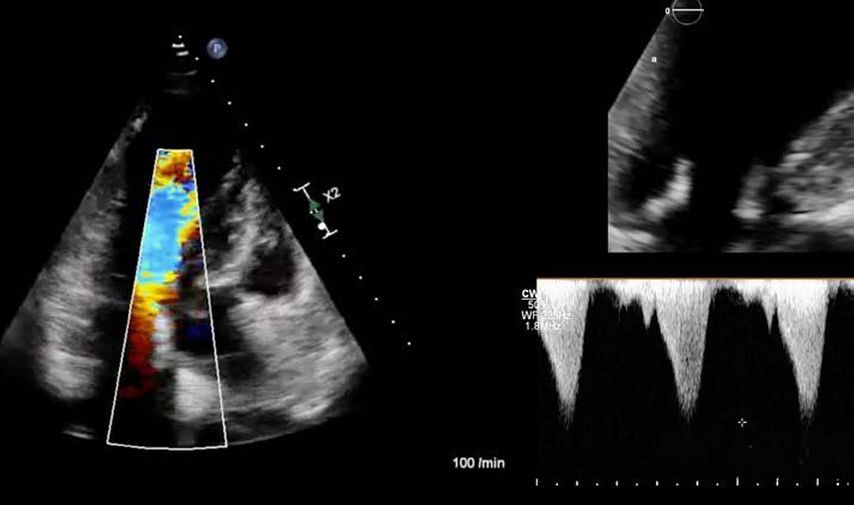

Im Echolabor des Pyhrn-Eisenwurzen Klinikums Steyr wird jede Form der Myokardwandverdickung mittels einer vollständigen Standardechokardiografie untersucht.2 Dabei wird auch ein Fokus auf die kontrastmittelunterstützte Sonografie gelegt, um die tatsächliche Dicke des Myokards zu vermessen.3 Die Verdickung sollte optimalerweise mittels 3D-LV-Massenmessung erfolgen. Die Messung im 2D-Bild ist dahingehend unterlegen. Ebenso wird jede Myokardwandverdickung mittels 2D-„strain imaging“ in der transthorakalen Echokardiografie (TTE) untersucht.4–6 Der „strain“ ist eine Messung der longitudinalen Funktion des Herzens (Video 1).

Bei der hypertrophen CMP gibt es die Besonderheit, dass versucht werden muss, einen Ausflusstraktgradienten (LVOTO) zu messen, da dieser für die Prognose und Therapie relevant ist.1 Eine neue Therapie der hypertrophen obstruktiven CMP (HOCMP) sind kardiale Myosininhibitoren. Diese können zu einem „reverse remodeling“ des Herzens führen und Parameter, wie den „strain“, neben der Reduktion des Ausflusstraktgradienten unter Therapie deutlich verbessern.1,8,9

1. Fall: HCMP vs. HOCMP, männlich 52a

Der erste Fall beschäftigt sich mit einem Patienten mit einer hypertrophen Kardiomyopathie (HCMP). Er gibt eine deutliche Belastungsdyspnoe sowie einen ausgeprägten Leistungsknick an. Es wurde infolgedessen eine Untersuchung mittels standardisierter Echokardiografie inklusive „strain imaging“ durchgeführt. Der globale longitudinale „strain“ (GLS) mit –16% in Ruhe war gering reduziert. Es konnte kein relevanter LVOT-Gradient in Ruhe nachgewiesen werden. In der Belastungssituation (Handgrip, Valsalva, Kniebeugen und als Vorbereitung zur Untersuchung ein ausgiebiges Frühstück und Kaffee sowie ein am Vorabend konsumiertes Bier) konnte bei Kniebeugen mit einer Herzfrequenz von 126/min ein Spitzengradient bis 52mmHg dargestellt werden. Somit ergibt sich die Diagnose einer HOCMP mit einem belastungsinduzierten Gradienten. Bei bereits bestehender und ausgereizter Therapie unter Betablocker besteht die Indikation zur Therapie mittels des kardialen Myosininhibitors Mavacamten (Klasse-IIa-Empfehlung laut ESC).1 Darunter verbesserte sich die klinische Situation des Patienten deutlich, der Patient konnte uneingeschränkt Sport ausüben. Über die Zeit kam es zu einer geringen Reduktion der LV-Masse und einer geringen Zunahme des LV-„strain“. Die Belastungssituation zeigte durchwegs normale „strain“-Werte mit –20% (mit regionaler Reduktion bei Myokardwandverdickung im Sinne einer Hypertrophie). Die myokardiale Arbeit beim konkreten Patientenfall ist ebenso in Ruhe im grenzwertigen und unter Belastung im guten Normalbereich.6,8,9 Der Patient ist derzeit unter 5mg Mavacamten einmal täglich optimal eingestellt. Die EF in Ruhe ist konstant bei 50–55%. In Video 2 werden unterschiedliche Gradienten dargestellt, um eine HOCMP mit LVOTO von z.B. einer Mitralklappeninsuffizienz zu unterscheiden.Die Verdachtsdiagnose wurde mithilfe der Echokardiografie gestellt und durch das septal betonte „patchy“ LGE im MRT bestätigt.1,5